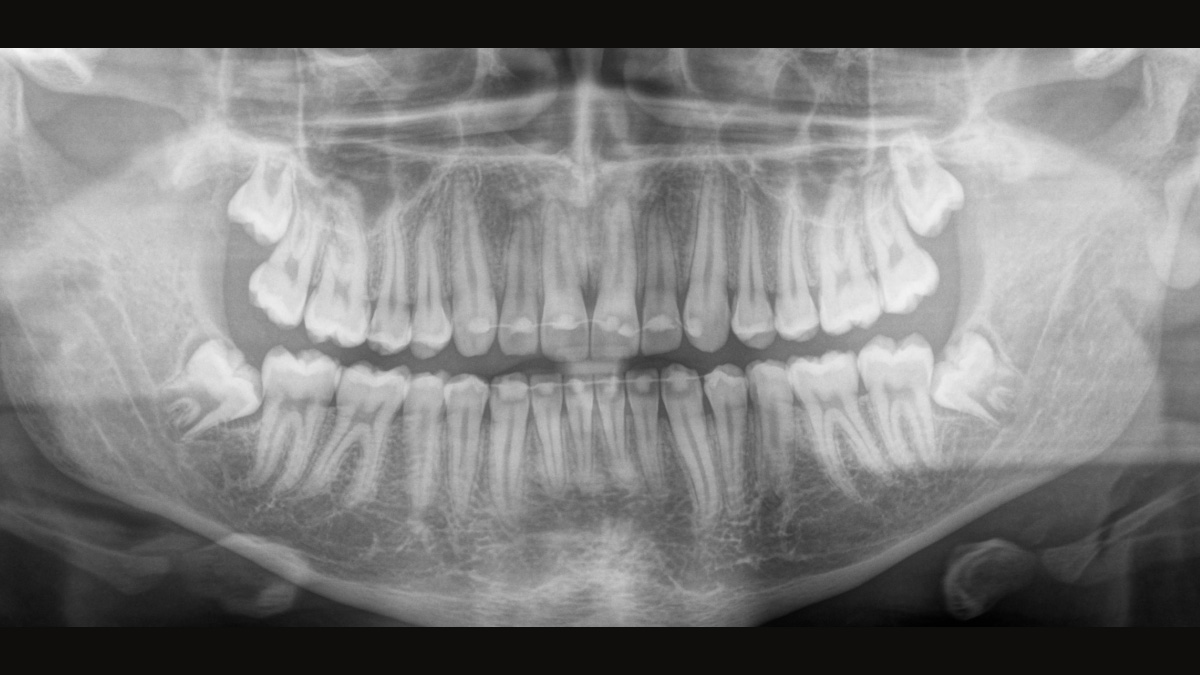

El sensor de conversión directa (Direct Conversion Sensor, DCS) ha revolucionado el estándar de la imagen panorámica. Las imágenes radiológicas se convierten directamente en señales eléctricas. Por lo tanto, no hay pérdida de señal debido a conversión de la luz, como es el caso de los sistemas convencionales. El resultado: imágenes con un alto nivel de nitidez y contraste, incluso con una dosis de radiación extremadamente baja. Para obtener información de diagnóstico precisa a fin de apoyar el tratamiento objetivo.

La imagen a continuación muestra una radiografía panorámica con y sin tecnología DCS. Usando la flecha, arrastre el control a través de la imagen para ver la diferencia que el sensor de conversión directa hace con la calidad de la imagen y las posibilidades de diagnóstico.

El enfoque correcto es crucial para excelentes radiografías panorámicas. Con la función de autofoco, usted recibirá automáticamente una imagen con la mejor nitidez posible en foco. Los dispositivos de radiología de Dentsply Sirona toman varios miles de imágenes individuales en un ciclo e identifican automáticamente las áreas donde la mandíbula está posicionada de manera óptima. Luego, sin ningún paso manual adicional, estas imágenes se muestran en una nítida imagen final.